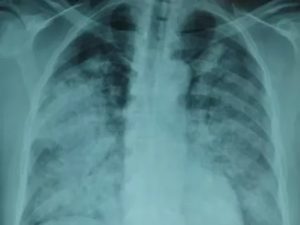

Расшифровать данные рентгеновского снимка способен только опытный рентгенолог. Также необходимо знать, что основным рентгенологическим признаком воспаления легких является участок или участки затемнения легочного поля. Однако, здоровые легкие на снимке имеют темный цвет, в то время как затемнения являются белыми участками.

Теперь рассмотрим различные виды пневмонии на фото рентгеновских снимков.

Данному виду патологии свойственно поражение небольших участков легочной ткани.

Изображение очаговой пневмонии прослеживается плохо, затемнения могут быть средней или вовсе слабой интенсивности.

Размеры очагов поражения в среднем достигают полутора сантиметров, при отсутствии лечения их количество увеличивается. На фото ниже изображен пример правосторонней очаговой пневмонии.